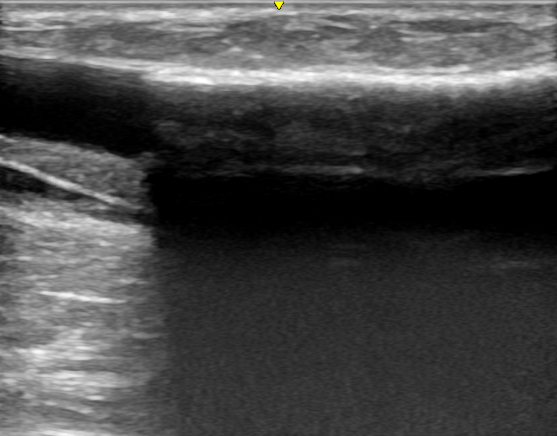

【覆膜|肾脏内科实施陕西省首例超声引导下透析通路支架植入术】近日 , 西安交通大学第一附属医院肾脏内科透析通路团队为一位人工血管内瘘狭窄的患者成功实施了超声引导下覆膜支架植入术 , 这是陕西省首例在超声下进行的此类手术 , 标志着西安交大一附院透析通路介入治疗技术的又一次提升 。 患者为男性 , 55岁 , 诊断为慢性肾炎 , 慢性肾功能衰竭 , 使用左前臂人工血管内瘘规律透析1年 。 该患者此前因为人工血管内瘘狭窄曾接受两次经皮静脉球囊扩张术(PTA) , 但术后狭窄很快复发 , 对于这种狭窄容易复发且单纯PTA效果不佳的患者 , 覆膜支架植入术是比较好的解决方法 。 经过充分的术前准备和一个小时的手术 , 肾脏内科杨世峰副主任医师及其团队成功为该患者实施了超声引导下覆膜支架植入术 , 术后患者人工血管内瘘血流恢复通畅 , 透析过程中血流量充足、静脉压正常 , 达到了较好的手术效果 。

血液透析通路是尿毒症患者的“生命线” , 目前尿毒症患者最常用的透析通路是自体动静脉内瘘和人工血管内瘘 。 然而内瘘无法避免的并发症就是狭窄 , 长期高速的血流会引起血管内膜反应性增生 , 导致内瘘管腔狭窄和血流量不足 , 影响透析效果 , 狭窄严重时导致内瘘闭塞、血栓和失功 。 处理动静脉内瘘狭窄最有效的方法就是PTA , 通过血管腔内治疗的方法解除狭窄 , 具有创伤小、恢复快的优点 。 然而部分病例单纯PTA后狭窄容易短时间内复发 , 对于这些病例覆膜支架植入是较好的解决办法 。 传统的支架植入术是在DSA造影下进行 , 而超声引导下介入手术是近几年新兴的技术 , 超声引导具有方便、无辐射损伤 , 无造影剂损害、可显示闭塞病变等优点 , 特别适合动静脉内瘘等外周血管的介入治疗 。

随着近些年尿毒症患者数量的快速增长 , 透析通路的建立和维护工作也日益增多 。 为了满足临床诊疗的需要 , 西安交大一附院肾脏内科进行了专病和专业方向分组 , 成立了包括透析通路组在内的几个亚专业组 。 透析通路组成立后不断开拓新医疗技术 , 2016年率先在陕西省内开展各种超声引导下透析通路的介入治疗 , 包括内瘘狭窄球囊扩张术(PTA)、内瘘腔内取栓术、内瘘球囊扩张促成熟术、内瘘假性动脉瘤封堵修补术等 , 此次超声引导下覆膜支架植入术的开展使肾脏内科的透析通路介入治疗技术进一步完善 , 能更好地用于维护透析患者的透析通路 , 为透析患者的“生命线”保驾护航 。